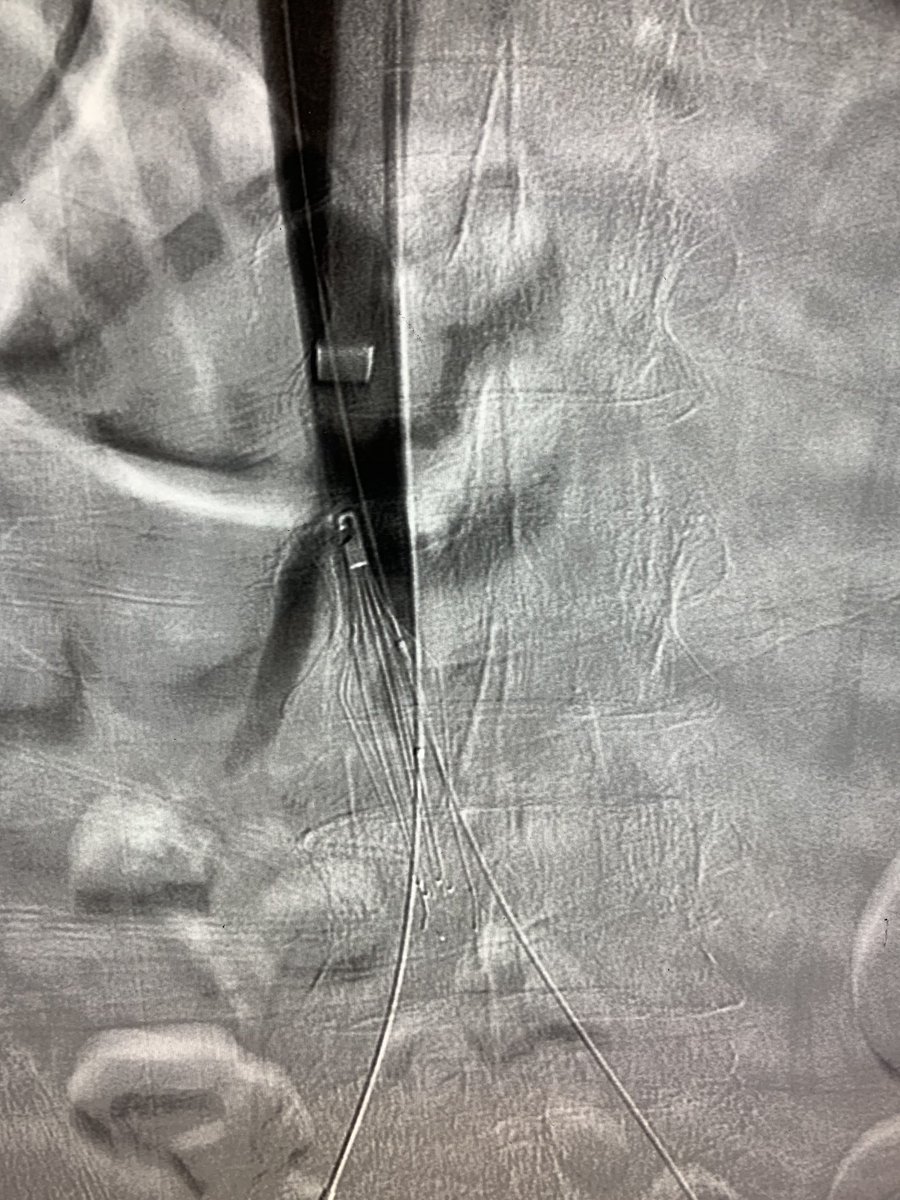

3 month old #IVCfilter with iliocaval occlusion, bilateral leg edema. Crossed both CIV occlusion from below, forceps #Filterout with 18Fr sheath then 18mm wallstent iliocaval reconstruction. #WeCanRecan

10

16

78